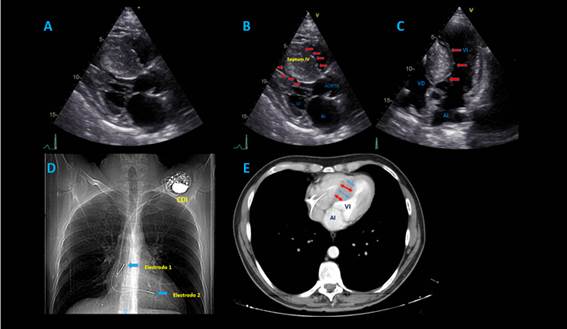

En junta médica se definió miectomía del septum interventricular, una vez descartado sustrato arrítmico y compromiso de fibra nerviosa pequeña de miembros inferiores como causa de pérdida del tono postural, procedimiento llevado a cabo sin complicaciones. En ecocardiograma posoperatorio hubo disminución significativa del grosor del septum interventricular y del componente obstructivo del tracto de salida del ventrículo izquierdo (figura 3). El paciente tuvo egreso hospitalario sin nueva documentación de síncopes.

Figura 3. A-B:  Ecocardiograma transesofágico, en imágenes multidimensionales donde se evidencia hipertrofia septal en vista de esófago medio con obstrucción al tracto de salida y presencia de SAM (movimiento anterior septal de válvula mitral). C: Posoperatorio de miectomía septal que demuestra liberación de la obstrucción del tracto de salida del ventrículo izquierdo. D: Vista de corrección de hipertrofia septal con reducción septal ventricular izquierdo.